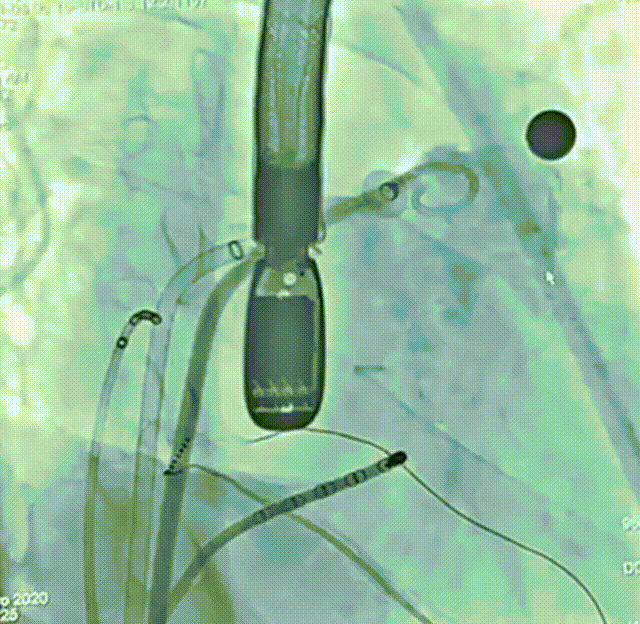

术前造影